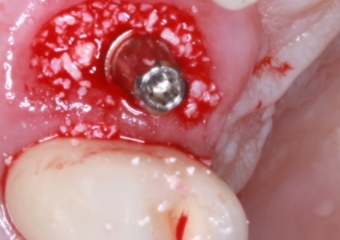

Foto implante   enxerto Bio Oss 03-10-16 - Clínica Cliniface

Foto implante enxerto Bio Oss 03-10-16